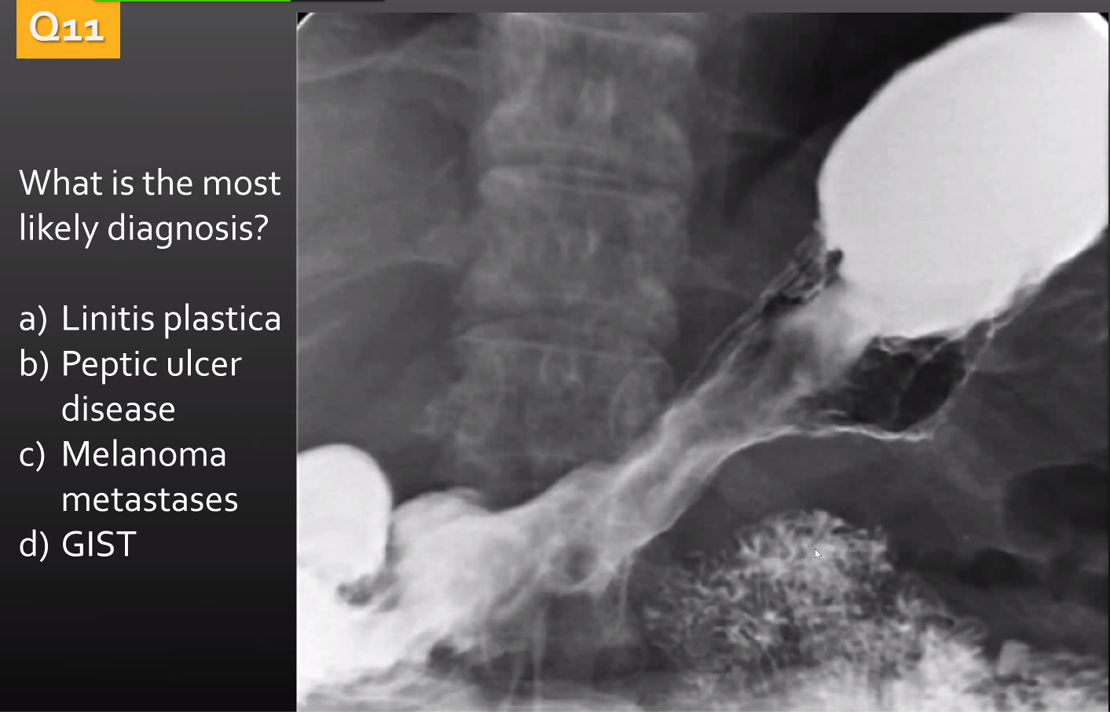

benign or malignant?

benign

malignant ulcer with a carmen meniscus sign